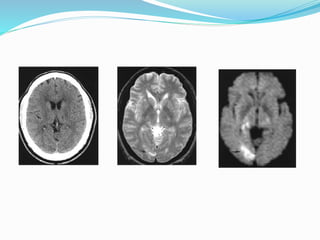

 MR Perfusion in Stroke

 Mismatch between PW and DW represent potentially

salvageable tissue (penumbra). PW-DW mismatch is

also indicator of clinical outcome. Small mismatch has

good clinical outcome. Large mismatch is associated

with poor clinical outcome and larger vessel occlusion.